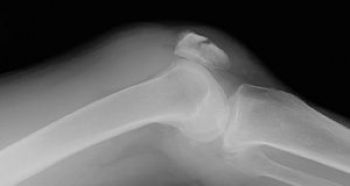

ɨ³¸¹ü¤È¤Ï

ɨ´ØÀá¤ÎÁ°Ì̤ˤ¢¤ë٨ʿ¤Ê¹ü¤Ç¤¹¡£

¼ï»Ò¹ü¤Î¤¦¤ÁºÇÂç¤Î¤â¤Î¤Ç¡¢Â¯¤Ë¡Ö¤Ò¤¶¤Î¤ª»®¡×¤È¤¤¤ï¤ì¤Þ¤¹¡£

¾åü¤Ë¤ÏÂçÂÜ»ÍÆ¬¶Ú¤¬¤Ä¤­¡¢²¼Ã¼¤Ë¤Ïæú¹üÁ°Ì̾åÉô¤È¤Î´Ö¤Ëɨ³¸¿ÙÂÓ¤¬¤¢¤ê¡¢

ɨ¤òư¤«¤·¤¿¤ê¡¢Êݸ¤ëÌò³ä¤ò²Ì¤·¤Æ¤Þ¤¹¡£

ɨ³¸¹ü¤Ï¡¢É¨¤ÎÁ°Ì̤ˤ¢¤ë¤¿¤á¡¢É¨´ØÀá¤ÎÊݸî¤Èɨ¤Î¿­Å¸¤ÎƯ¤­¤ò¼ê½õ¤±¤·¤Þ¤¹¡£

Èéɿľ²¼¤Ë¤¢¤ë¤¿¤á¡¢Â»½ý¤·¤ä¤¹¤¯¡¢¹üÀޤο¤¯¤Ï²£¹üÀÞ¤Ç秤ÎÃÇÎö¡¢¹üÊÒ¤ÎÎ¥³«¤òǧ¤á¤é¤ì¼ê½Ñ¤Ë¤Ê¤ê¤Þ¤¹¡£